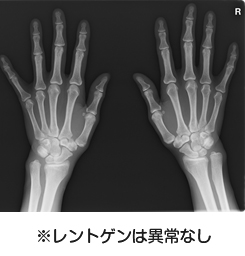

昔はレントゲンでリウマチの診断をしておりましたが、実はレントゲンでは骨しか見えないのです。

リウマチが最初に起きる肝心の関節の中は、残念ながらレントゲンでは写らないのです。そのためレントゲンでは早期のリウマチは診断がつかず、リウマチが進行して骨が壊れてから初めて診断となります。